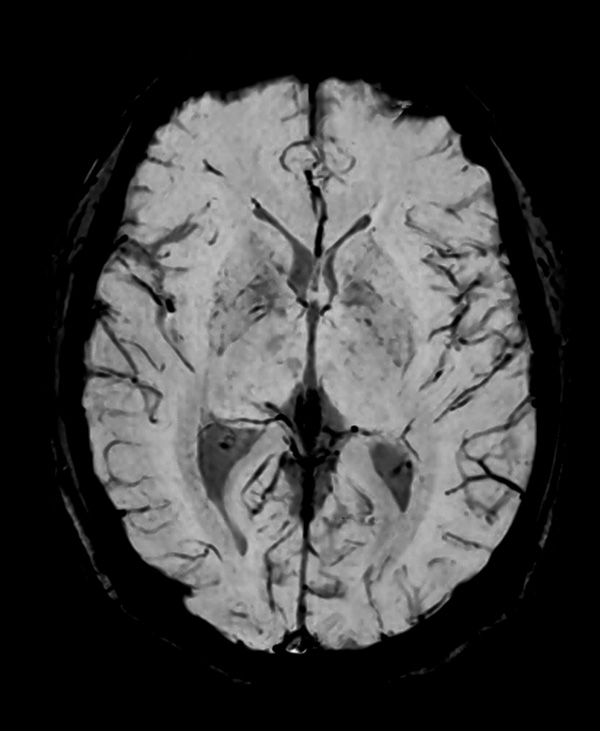

Comprehensive Brain imaging at 1.5T